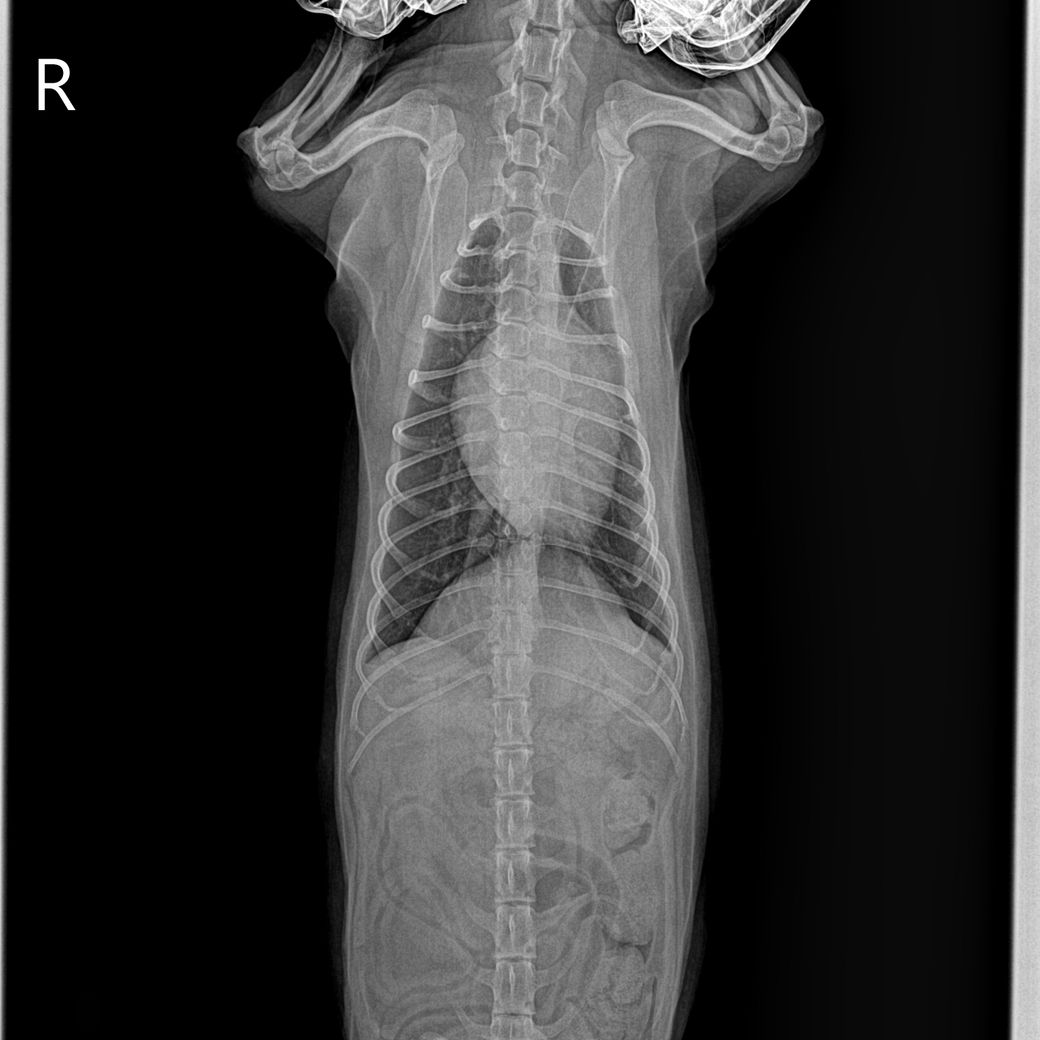

첫번째 사진이 1년전 다른병원에서 찍은 엑스레이고 2,3번째가 이번에 찍은 흉골 휜 엑스레이입니다.. 3,4번째 흉골 휜 엑스레이 같은 사진인데 휜 흉골부분 노란색으로 표시해뒀습니다. R, L사진 둘 다 다른방향에서 찍은거같은데, 둘 다 휘어있습니다. 폐쪽의 문제일수도 있을까요? 기침이나 식욕감퇴 등의 다른 증상은 없고 변 상태도 좋습니다.